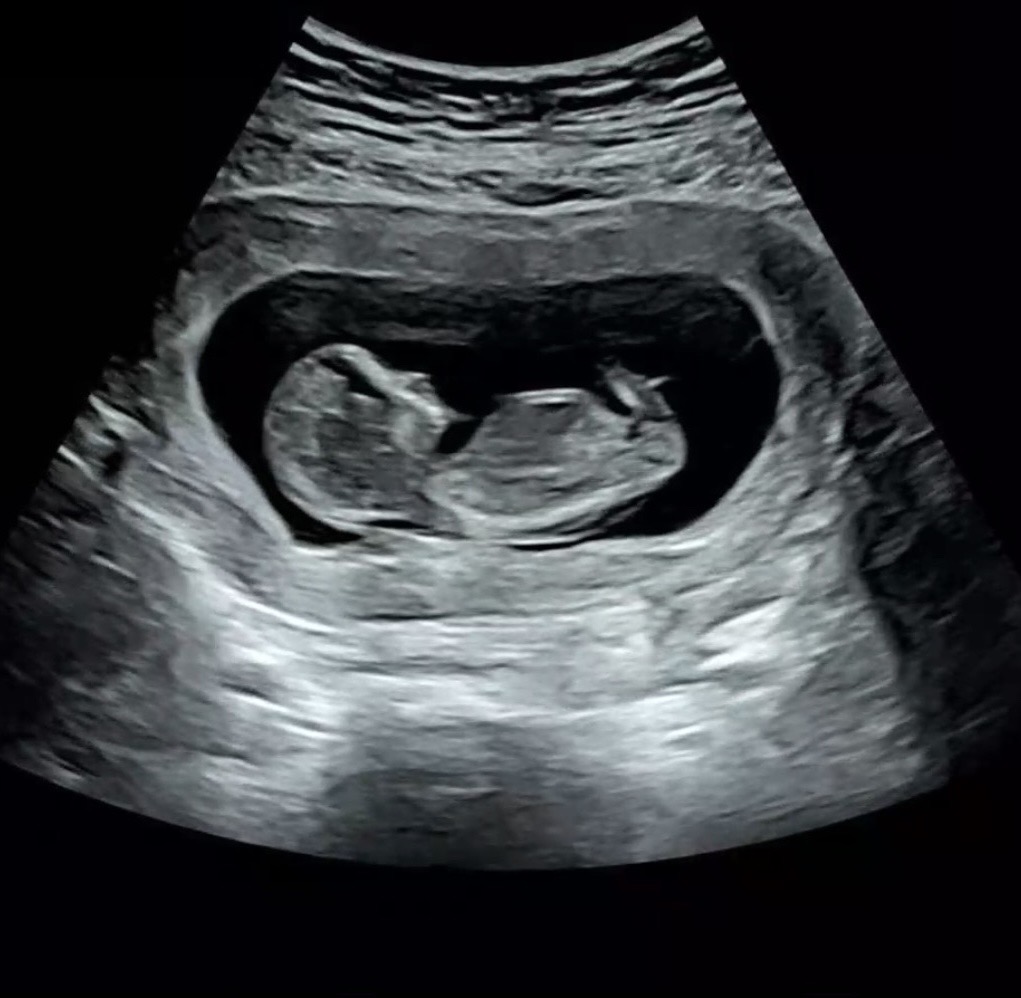

아들같은가요 딸같은가용??

아직 11주 6일이지만 아들같나요 딸같나용 ???